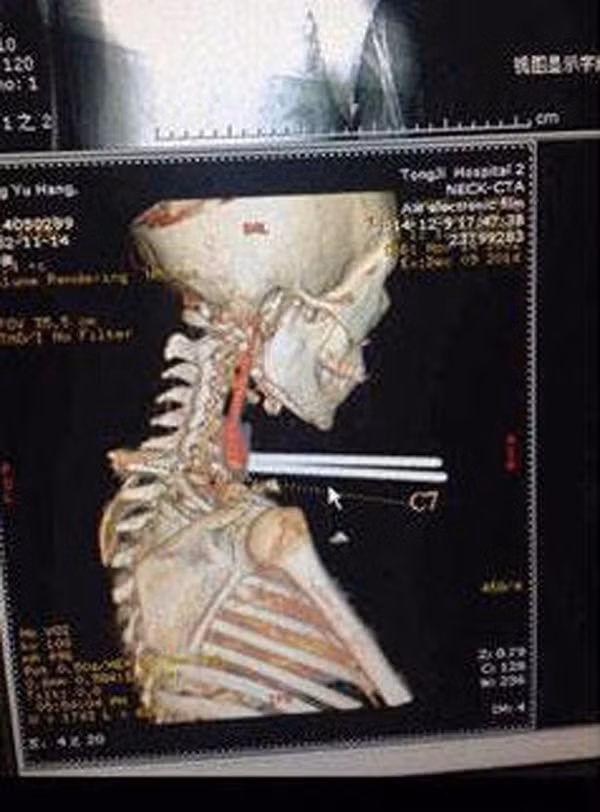

Anh Andrew Linn 28 tuổi tại Las Vegas Andrew, đã gặp phải vụ tai nạn có một không hai khi đang lái xe trong tình trạng buồn ngủ. Linn đã lao xe ra khỏi hướng đang lưu thông trước khi đâm phải hàng rào bằng kim loại. Các nhân viên cứu hộ đã phải cắt ống kim loại để đưa tài xế ra khỏi xe và chuyển khẩn cấp tới bệnh viện. Đội ngũ y tế tại đã có thể loại bỏ ống kim loại mà không gây hại đến động mạch cảnh và tĩnh mạch cổ.